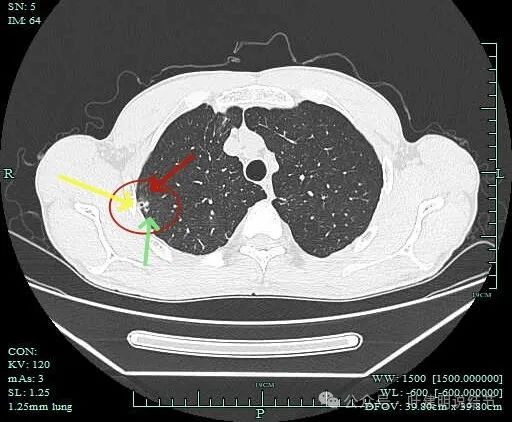

病灶似乎有卫星灶,中间有小空泡征,边缘有晕。

感觉周围略糊,有晕的感觉。

上面层面密度较高。

似乎有毛刺征,但膨胀性不明显。

有部分边缘显毛糙。

点状高密度,有晕的感觉。

点状高密度结节。

点状高密度之外,蓝色箭头示周围有淡磨玻璃影。

风轻云淡磨成分明显且轮廓不清。中间的点状高密度显得不够致密,缺乏收缩力。

边缘区仍有淡磨形态的晕